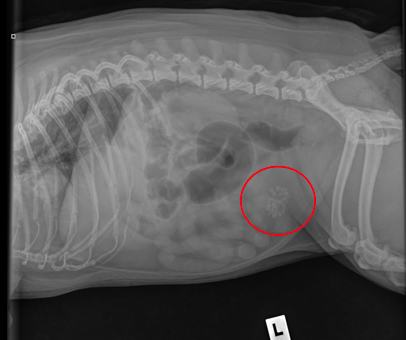

Diagnostic imaging discovered that Bonnie had a cluster of bladder stones. This was a clear sign that her infections had been ongoing and unresponsive to typical treatments.

Attached are Bonnie’s X-rays, which show a cluster of stones in her bladder—the

reason she was brought in. These were successfully removed through surgery.

Bonnie’s recovery was nothing short of inspiring. Her post-op x-rays show a bladder free from stones. Her revisits confirmed what we hoped — no more signs of infection.